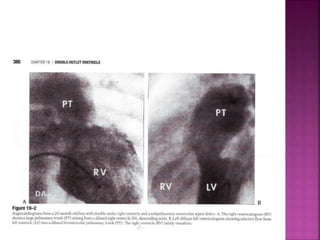

 CXR

Pulmonary vascularity increased, CCF

LA ,LV enlarged, pulmonary trunk dilated seen prominently (

side by side great vessels), when pulm trunk posterior ..

Not border forming (resembles TGA)

With onset of pul vasc disease LV volume load curtailed

Pulmonary trunk dilation persists (resembles non res VSD

with Eisenmenger)